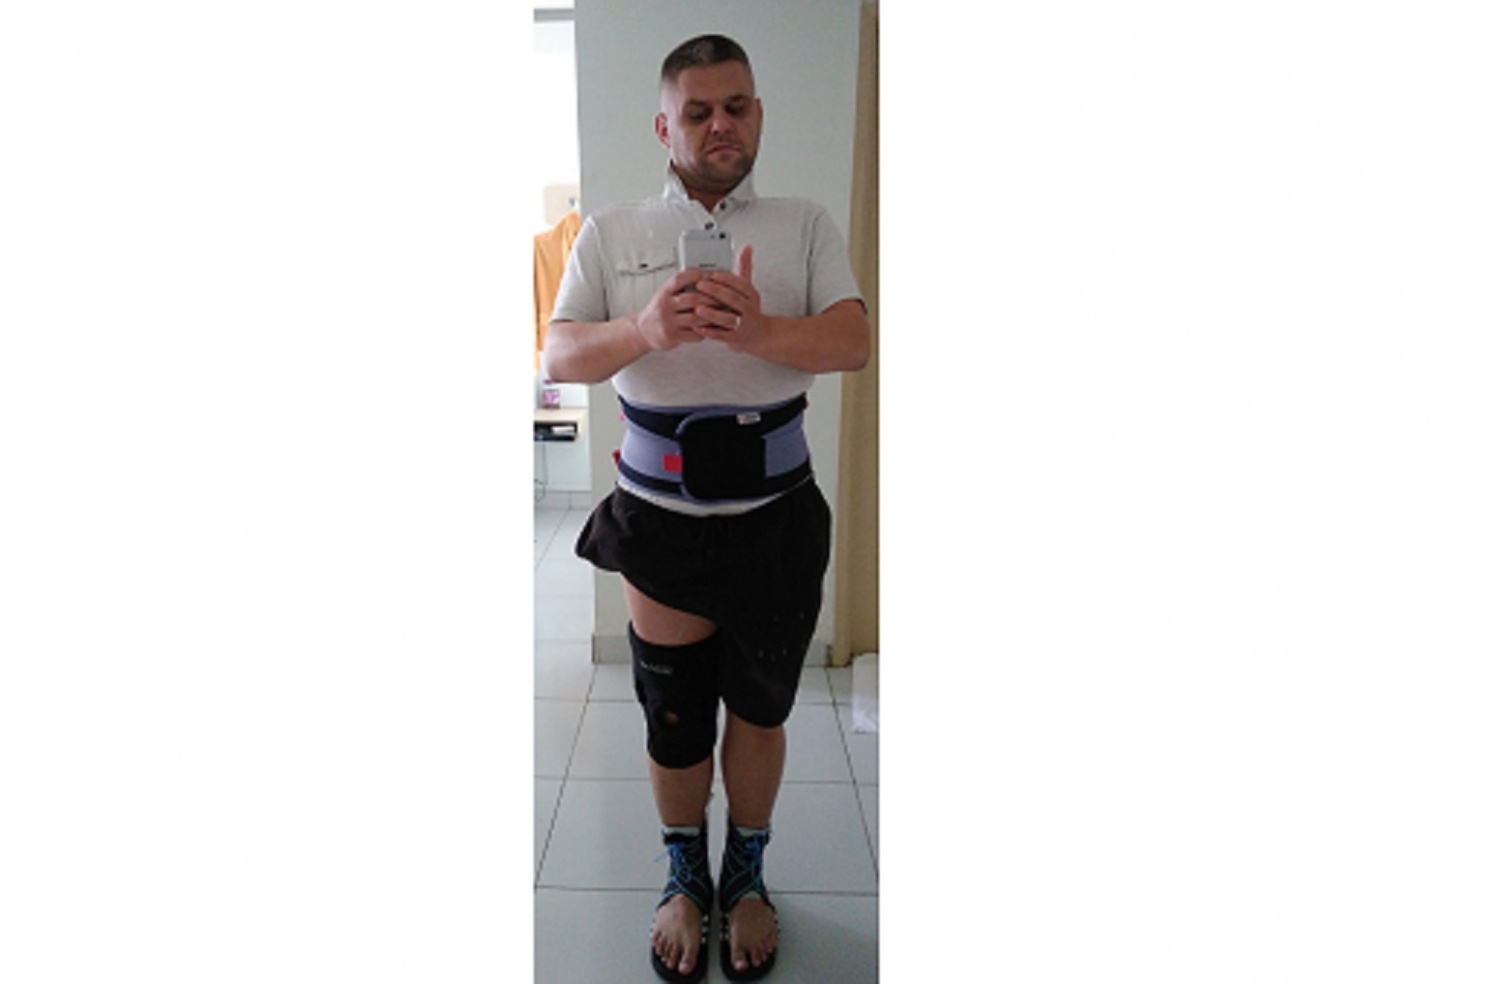

Pomijając aspekt estetyczny, spowodowało to problemy z przełykaniem i mówieniem, ponieważ każdy ruch żuchwy sprawia ogromny ból. Niesymetryczne używanie mięśni szyi oraz niewłaściwa pozycja języka z każdą chwilą powoduje problemy z utrzymaniem krtani we właściwej pozycji. Niewłaściwa pozycja podniebienia i żuchwy powoduje przesunięcie środka ciężkości głowy oraz zaburzenia równowagi, co w następstwie powoduje zwyrodnienie kręgosłupa, w największym stopniu odcinka szyjnego, który na dzień dzisiejszy mam uszkodzony (kręgi od C3 do C7) w stopniu krytycznym i w każdej chwili grozi mi paraliż.

Przez niewłaściwą pozycję głowy kręgosłup na całej długości ulega deformacji, to ma również wpływ na kończyny dolne, które żeby utrzymać mnie w pozycji pionowej muszą poruszać się w niewłaściwy specyficzny sposób. To wszystko powoduje zwyrodnienie stawów, odrętwienie kończyn oraz ból czasem trudny do zniesienia.

Aesthetically aside, this made swallowing and speaking problems difficult, as every movement of the jaw is extremely painful. The asymmetrical use of the neck muscles and the incorrect position of the tongue every moment cause problems with keeping the larynx in the correct position. The improper position of the palate and the mandible causes a shift in the center of gravity of the head and imbalance, which in turn causes degeneration of the spine, especially in the cervical segment, which I have today is critically damaged (vertebrae from C3 to C7) to a critical degree and I am at risk of paralysis at any time.

Due to the wrong position of the head, the spine is deformed along its entire length, it also affects the lower limbs, which must move in the wrong specific way to keep me upright.